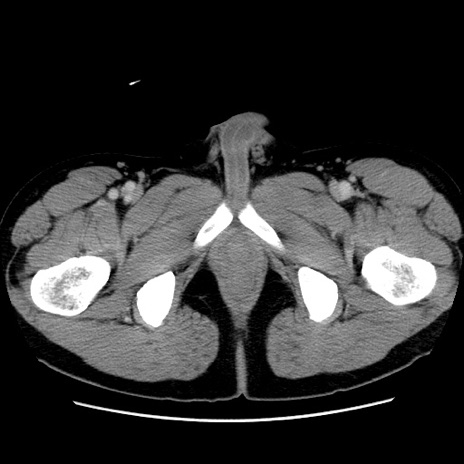

症例4(横断像)

【症例】30歳代男性

【主訴】腹痛、嘔吐

【現病歴】昨晩から突然の腹痛あり、その後嘔吐、軟便も出現。腹痛が改善しないため救急搬送となる。2日前にしめ鯖の食事歴あり。

【身体所見】意識清明、苦悶様、BP 135/90mmHg、BT 35.7℃、腹部:平坦、やや硬、心窩部〜臍部に自発痛、圧痛あり、筋性防御+、反跳痛-

【データ】WBC 8100、CRP 0.57